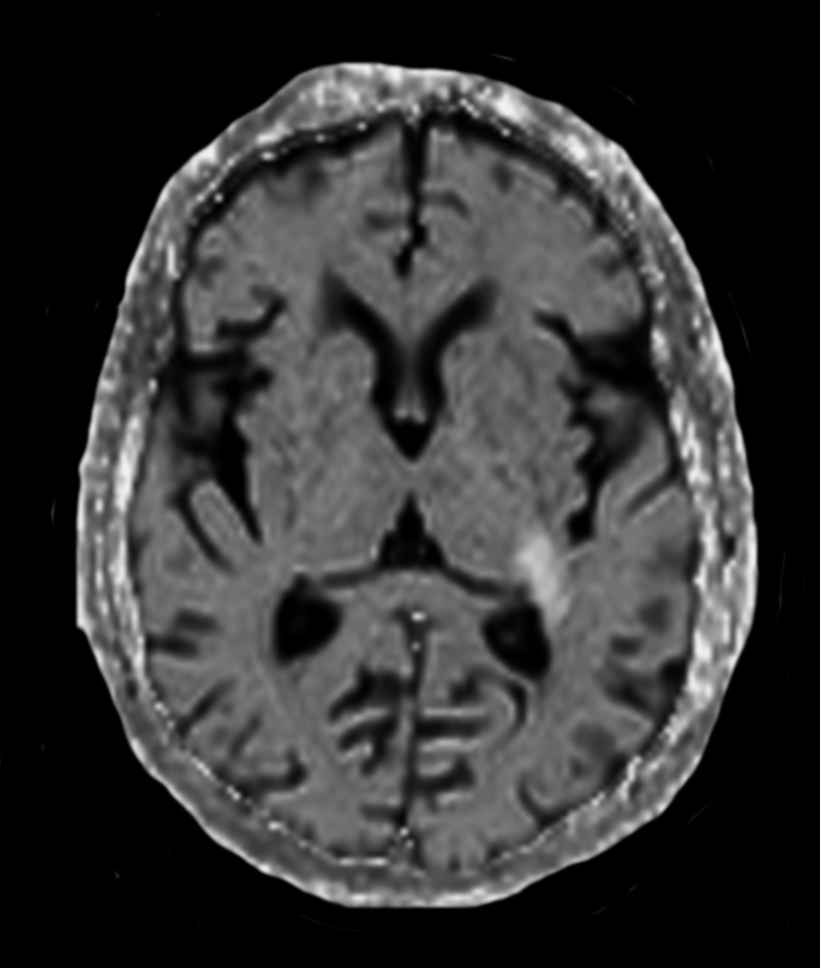

3D VIEW - T1w TFE (axial reformat)